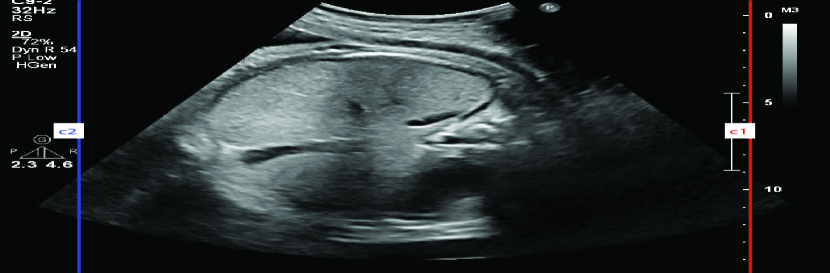

TABLE I: Sample outputs comparing reference captions with captions generated by the proposed model.

Uterine Ultrasound Image Reference Caption Generated Caption

[Uncaptioned image] a white straight line at the top center that represents the femur bone it is possible to calculate the femur length the knee is straight a white line at the top center that represents the femur bone it is possible to calculate the femur length the knee is straight

Consequently, the CNN-BiGRU model outperformed the other baseline models regarding BLEU and ROUGE scores and demonstrated lower loss values, underscoring its effectiveness in this application. Moreover, Table I provides further evidence by illustrating sample outputs that compare reference captions with captions generated by the CNN-BiGRU model. This comparison vividly showcases the model’s ability to generate high-quality captions through its robust bidirectional processing capabilities.